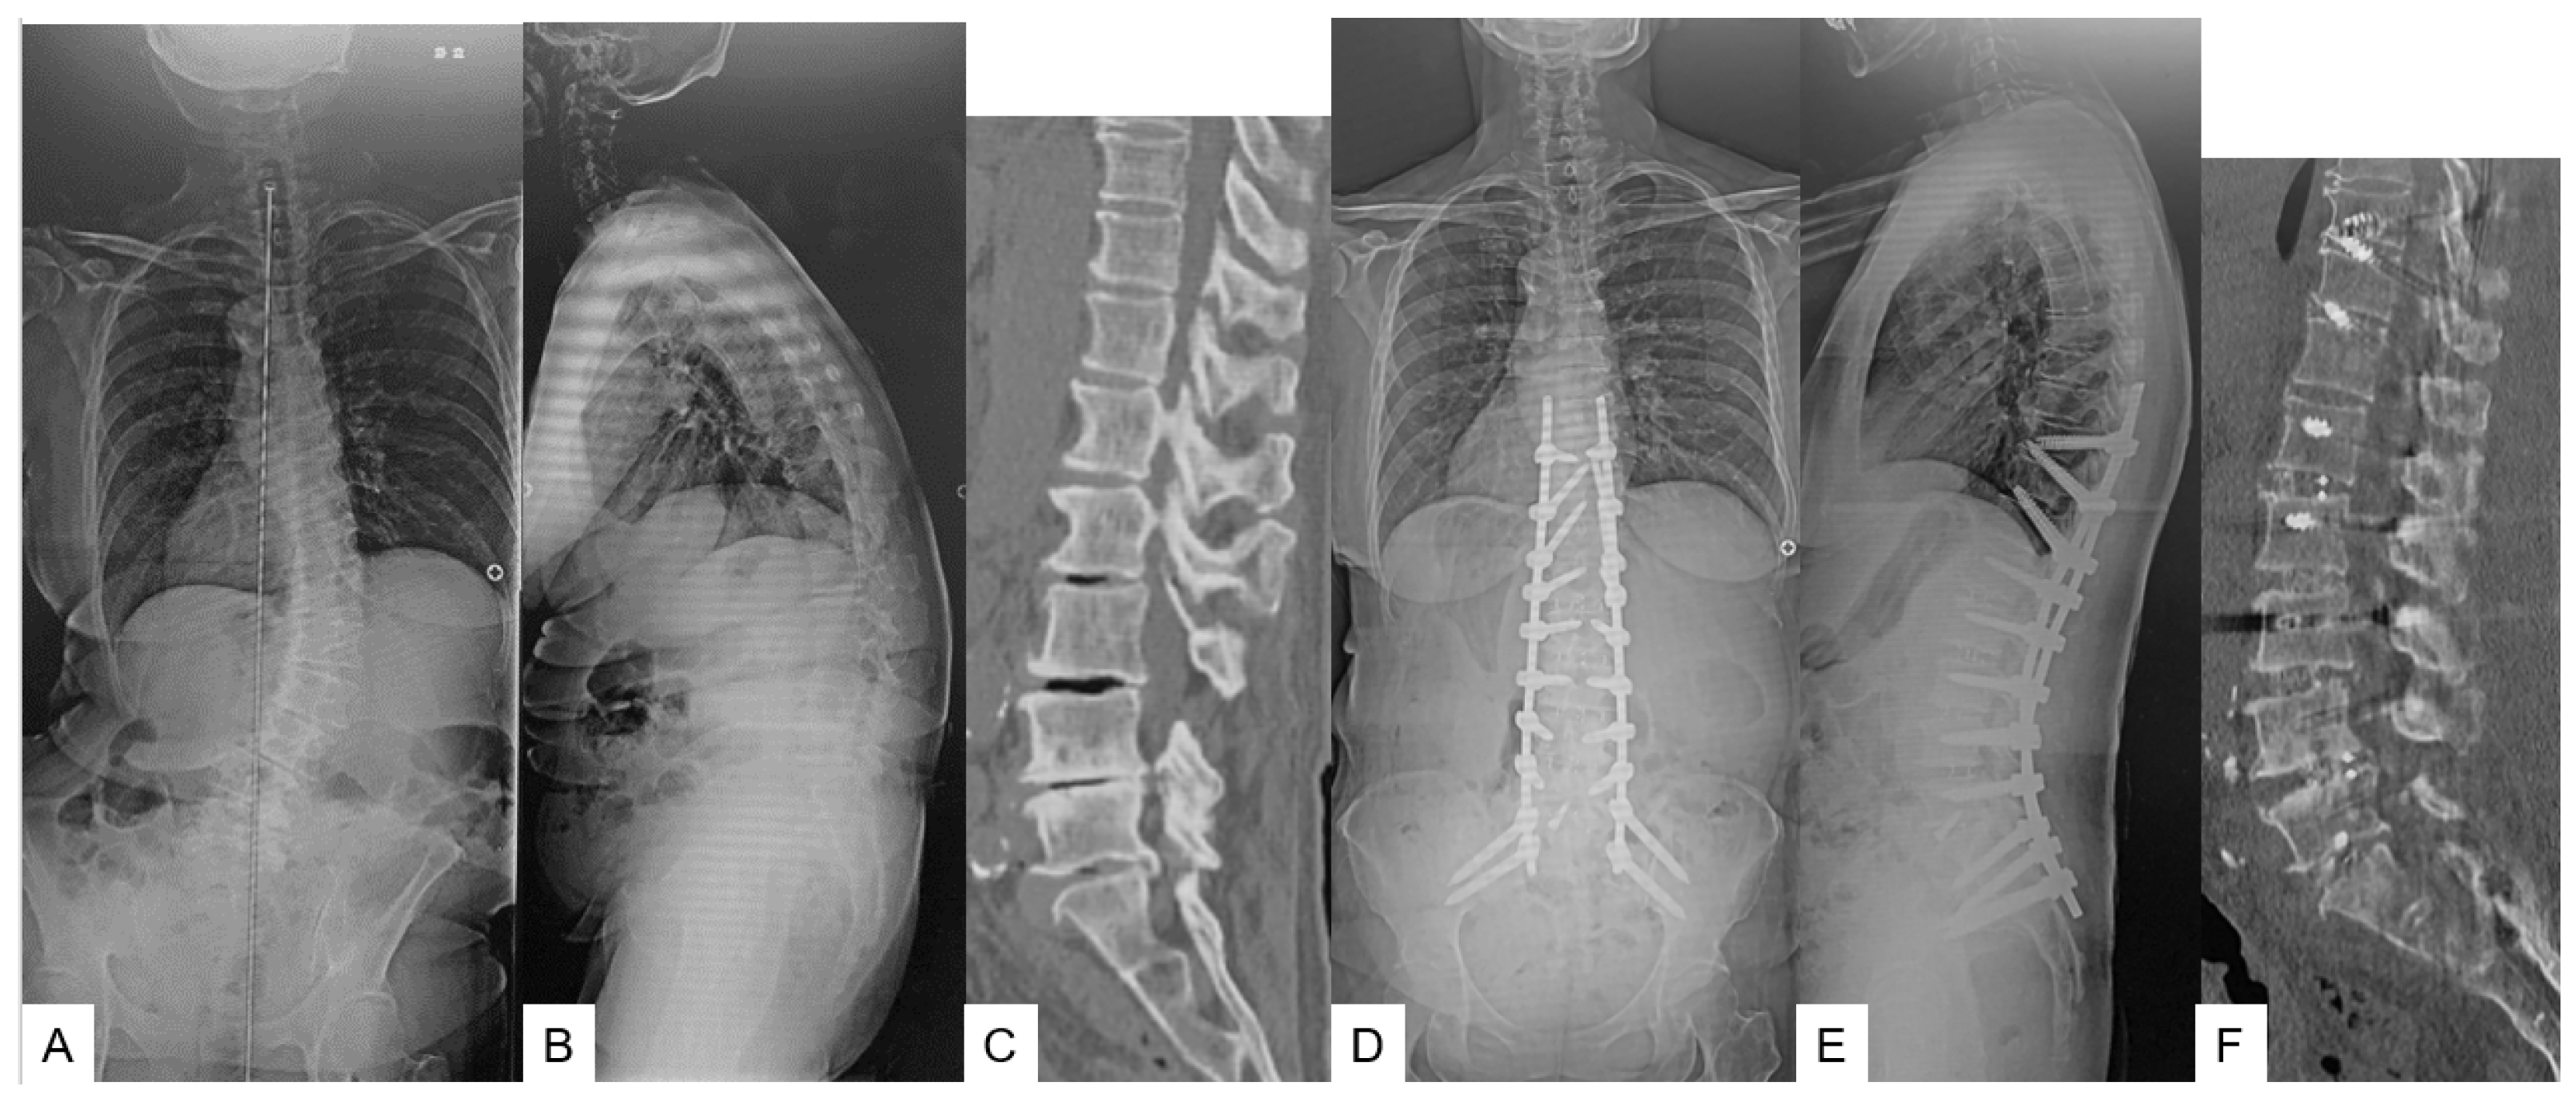

2.1.1. Primary Surgery (OLIF L1-S1 in Group O or OLIF L1-5 in Group T) (Figure 1) [9]

2.1.2. Secondary Surgery (T10-SAI in Group O or T10-SAI + TLIF51 in Group T) (Figure 1)